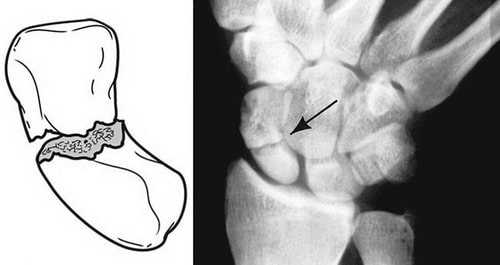

Переломы ладьевидной кости обычно классифицируются в зависимости от локализации в пределах кости. Наиболее часто перелом происходит в центральной части кости, называемой «талией». Также возможны переломы проксимального или дистального полюса ладьевидной кости.

Переломы подразделяются в зависимости от выраженности смещения фрагментов.

- Переломы без смещения. При таких переломах фрагменты кости сохраняют свое правильное положение.

- Переломы со смещением. При этих переломах костные фрагменты смещаются, между ними может формироваться промежуток или они могут накладываться друг на друга.

Схематичное изображение и рентгенограмма перелома ладьевидной кости в области ее «талии». Это наиболее частая локализация перелома.